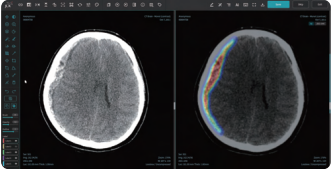

[로이슈 전여송 기자] 의료 AI 1호 상장기업 제이엘케이(대표 김동민)가 올해 본격적인 미국 진출 계획의 일환으로 현지에서 수요가 많은 CT영상 기반 뇌 경막하 출혈 분석 솔루션 JLK-SDH를 새롭게 출시하며 뇌출혈 진단에 필요한 CT기반 AI 솔루션의 세분화 및 전문성이 강화된 제품 라인업을 완료했다고 29일 밝혔다.

JLK-SDH는 뇌를 둘러싸고 있는 경막 내부 혈관의 파열로 인한 출혈을 진단할 수 있는 솔루션으로 주로 낙상이나 교통사고 등 외상으로 인해 발생하는 경막하 출혈 환자의 신속하고 정확한 병변 분석을 위해 개발됐다. 일반적으로 경막하 출혈 환자는 두부 외상으로 응급실로 이송되는 경우가 빈번하기에 가장 먼저 CT 촬영을 진행해 진단을 하고 치료 계획을 수립하게 된다.

기존 출시된 뇌출혈 진단 솔루션인 JLK-ICH가 주로 전반적인 급성 뇌출혈 진단에 강점을 보인 반면 이번에 출시된 JLK-SDH는 CT에서 신호강도가 강하지 않아 정상 뇌와 구분이 어려운 아급성(subacute) 혹은 만성 경막하출혈 데이터 학습에 공을 들여 어려운 뇌출혈 진단에 강점이 있다고 회사 측은 전했다.

사측은 이번에 개발된 JLK-SDH 솔루션이 응급 상황에서 의료진에게 신속하고 정확한 진단을 내리는 데 큰 도움이 될 것이라고 설명했다. 교통사고나 폭행 등 심각한 두부 외상으로 인한 급성 경막하 출혈은 시간과의 싸움이라고 할 수 있을 정도로 빠른 진단과 치료가 절실하다. 응급실에 도착한 환자가 이미 혼수상태에 빠져 있는 경우도 많고 출혈이 지속되면 뇌사상태까지도 이어질 수 있는 만큼 JLK-SDH 솔루션을 통해 골든타임을 확보하는 데도 큰 역할을 할 것으로 기대했다.